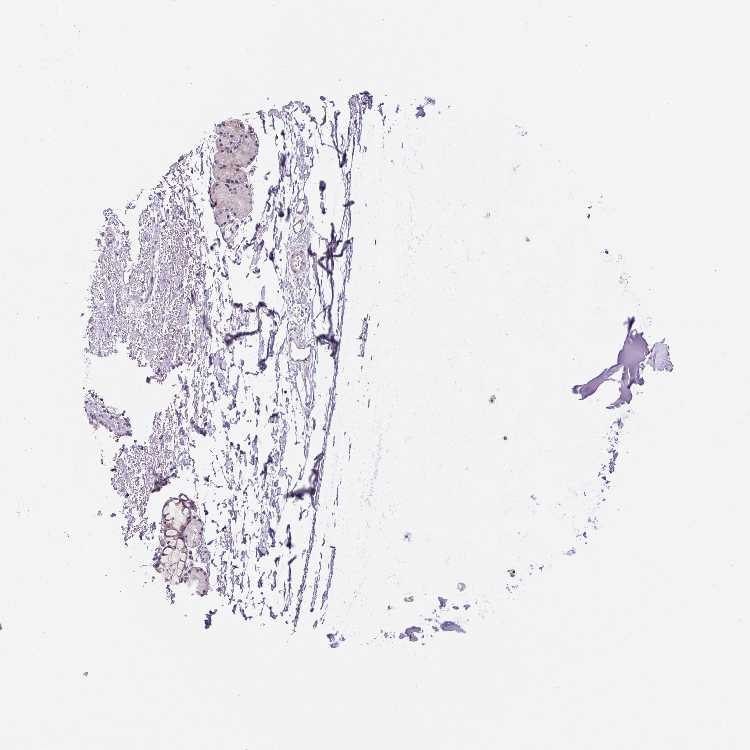

SOFT TISSUE 1 - Antibody stainingi

Antibody staining in the annotated cell types in the current human tissue is reported as not detected, low, medium, or high, based on conventional immunohistochemistry profiling in selected tissues. This score is based on the combination of the staining intensity and fraction of stained cells.

Each image is clickable and will lead to virtual microscopy that enables deeper exploration of all samples and also displays staining intensity scores, fraction scores and subcellular localization as well as patient and tissue information for each sample.

Antibody HPA045634Antibody HPA053812

Chondrocytes MediumMedium

Fibroblasts MediumNot detected

Peripheral nerve Low-

SOFT TISSUE 2 - Antibody stainingi

Chondrocytes -Medium

Peripheral nerve -Not detected